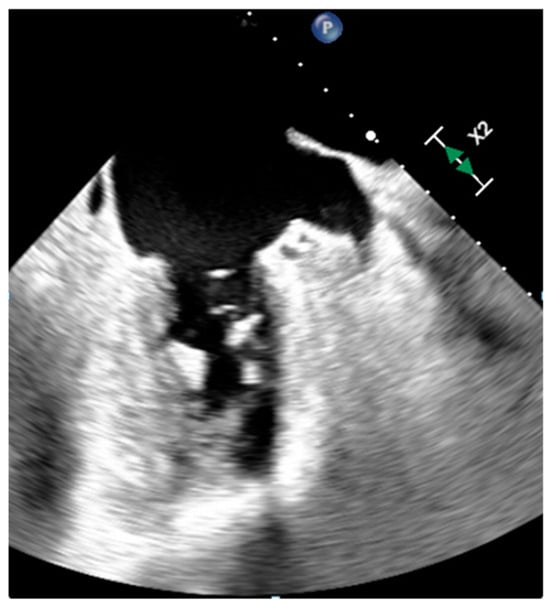

| Vegetations | Adulthood | Valves | Valve dysfunction, emboli, heart failure | Highly mobile, non-enhancing | Highly mobile, oscillating, protruding, valve dysfunction | Low attenuation, may recognize, perivalvular extension, fistulas, abscess | Highly mobile |

- Delgado, V.; Ajmone Marsan, N.; de Waha, S.; Bonaros, N.; Brida, M.; Burri, H.; Caselli, S.; Doenst, T.; Ederhy, S.; Erba, P.A.; et al. 2023 ESC Guidelines for the management of endocarditis. Eur. Heart J. 2023, 44, ehad193. [Google Scholar] [CrossRef]